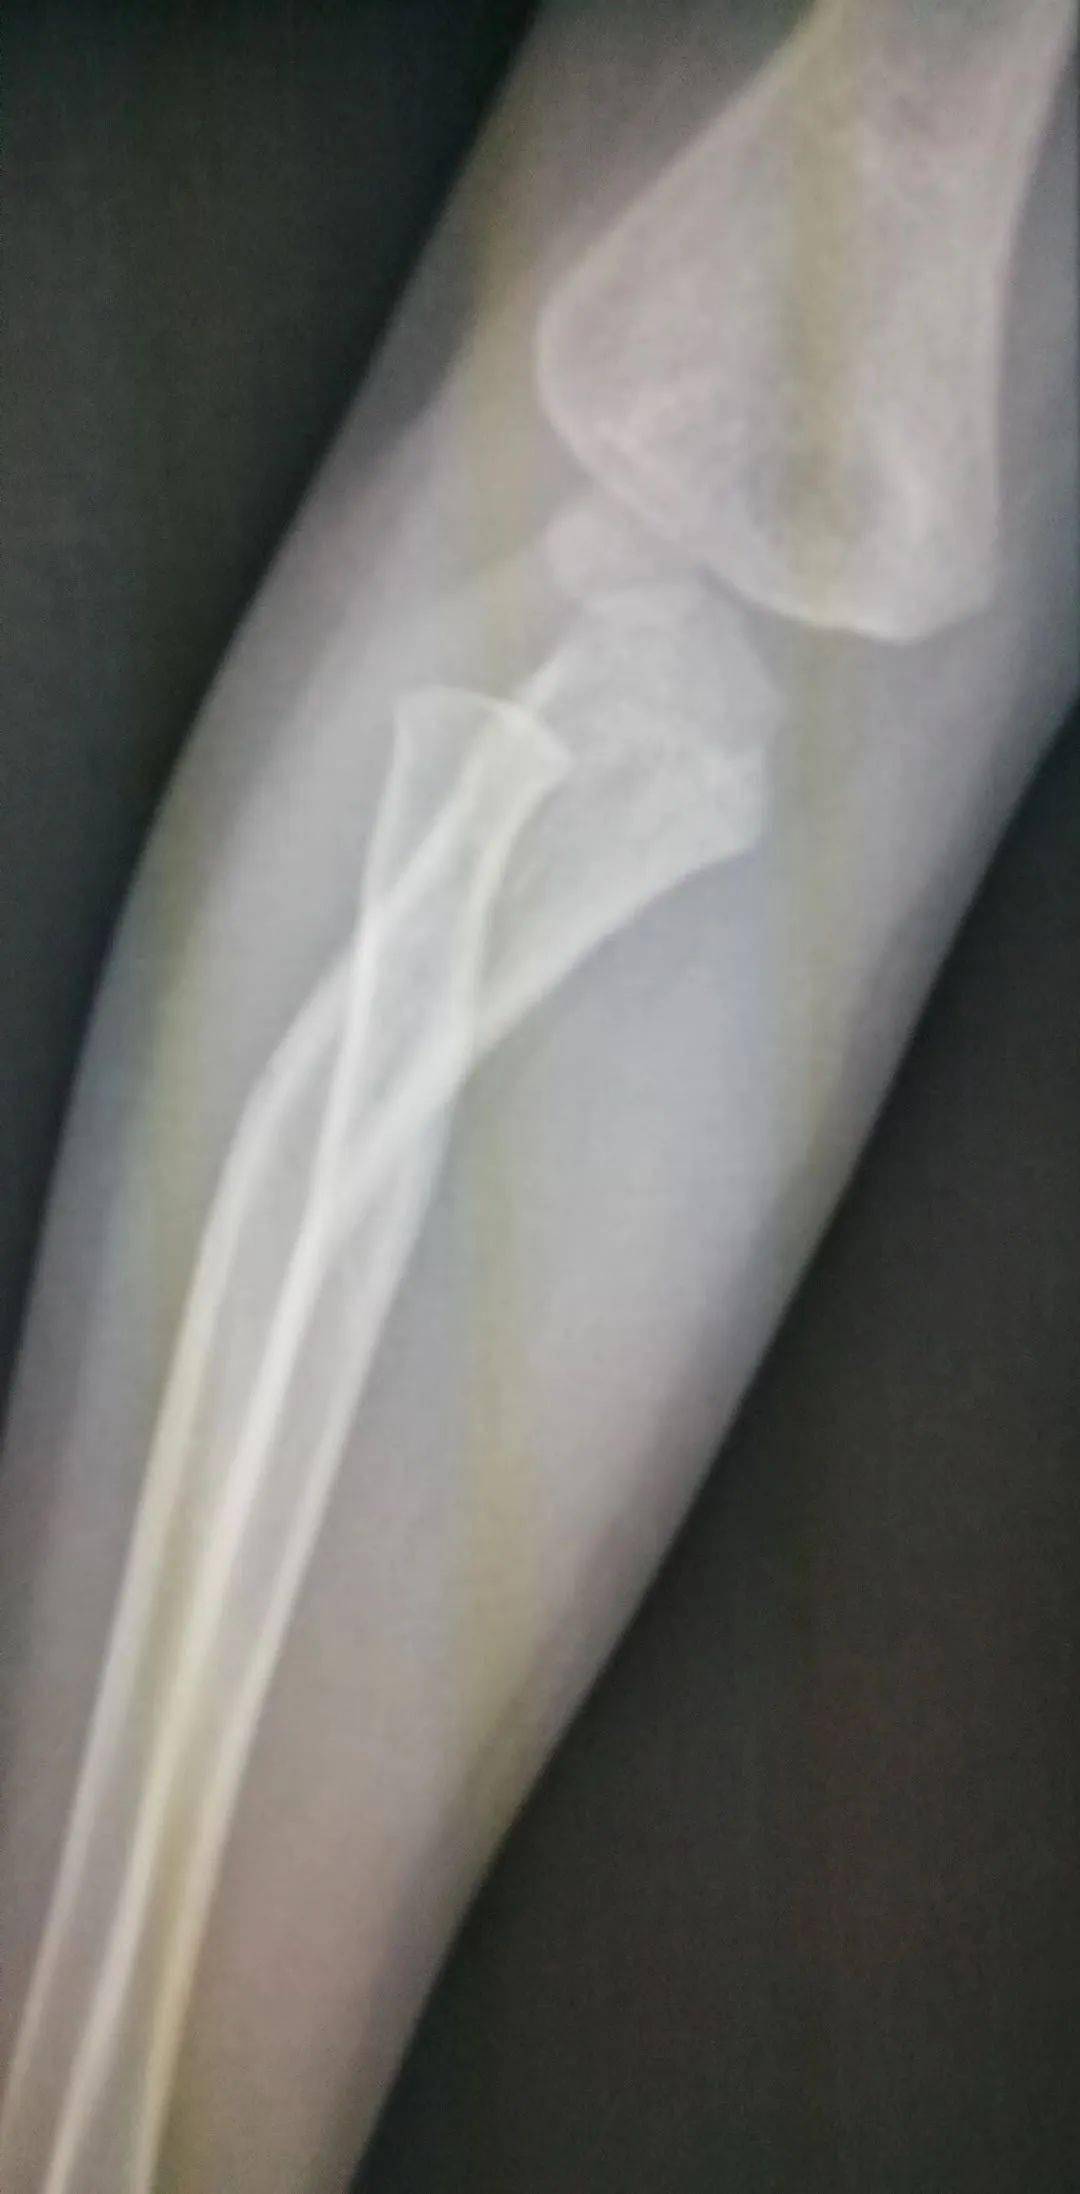

2、怎么看小孩有没有骨折图片